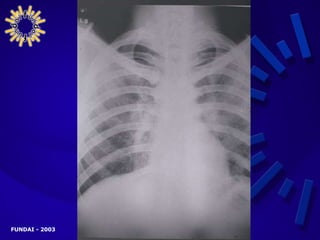

MANIFESTACIONES CLÍNICAS AVANZADAS PRESENTACIÓN RESPIRATORIA Tos Fiebre Disnea Expectoración Dolor torácico Manifestaciones extratorácicas